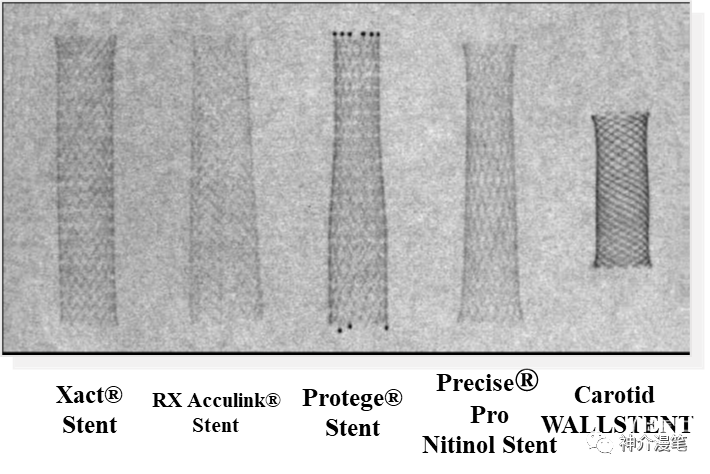

简要的几款主流颈动脉支架的汇总图

不同支架具有自己独特的特点,清楚地认识到各自的优缺点,才能更为精准的去选择,扬长避短,发挥最大的治疗效果。OK,接下来就简单分开介绍目前市场上的几大主流颈动脉支架,还是那句话,没有任何利益导向,纯学术探讨,而且更多的是个人理解,所以有不认同的,大家开诚布公的讨论,千万不要拍我的黑砖。